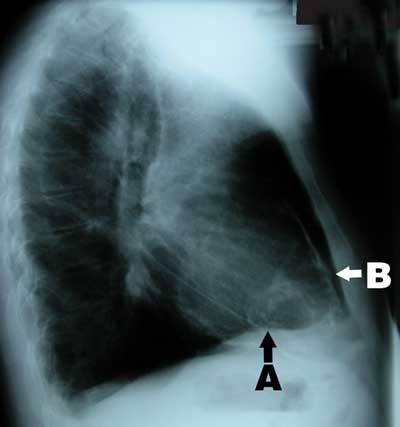

A 58-year-old man of British descent presented in 2003 with chest pain, facial flushing and elevated jugular venous pressure but no leg oedema. He had been exposed to tuberculosis in childhood, had a strongly positive tuberculin test and had been followed up in the tuberculosis surveillance program with regular chest x-rays, but had never been diagnosed with tuberculosis. Chest x-ray on presentation showed calcified plaques and masses in the pericardium and mediastinum (Box 1). Computed tomography revealed extensive calcification of the pericardium (Box 2). Coronary angiography showed 70% stenosis in the left anterior descending artery. Cardiac catheterisation showed equalisation of diastolic pressures in all four chambers, with a positive square root sign (pattern of ventricular diastolic pressure characteristic of constrictive pericarditis).